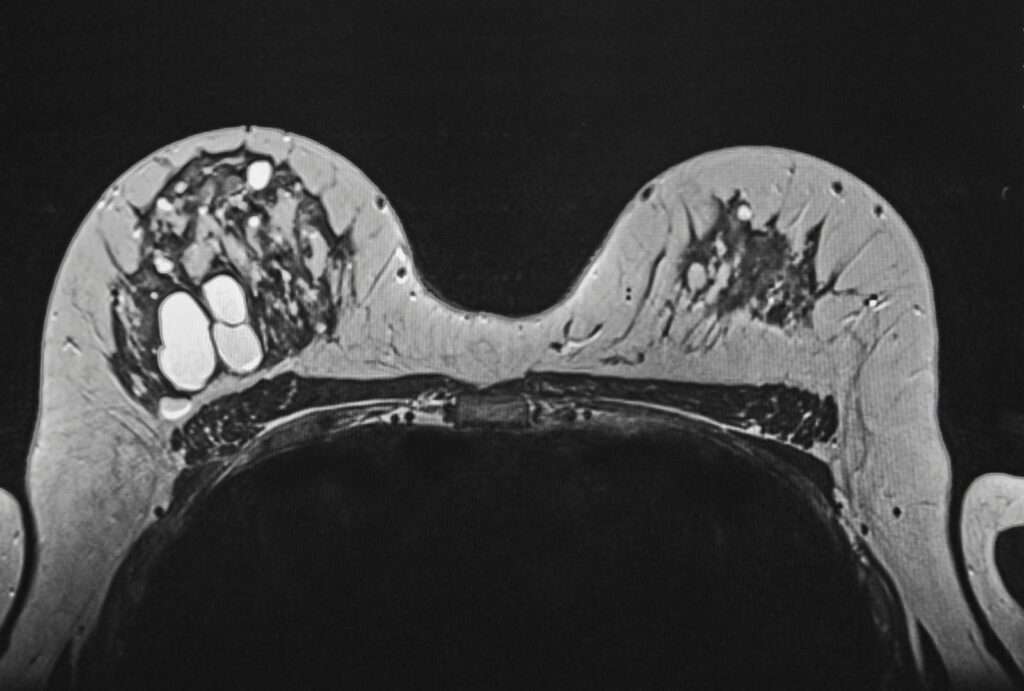

A mammogram is specialised medical imaging that uses a low-dose of x-ray to examine the breast for the early detection of breast cancer before symptoms appear. During the mammogram examination, the breast is gently compressed between two plates to spread out the tissue and ensure clear imaging. The procedure usually takes only a few minutes, but the results can provide valuable insights into a woman’s breast health.